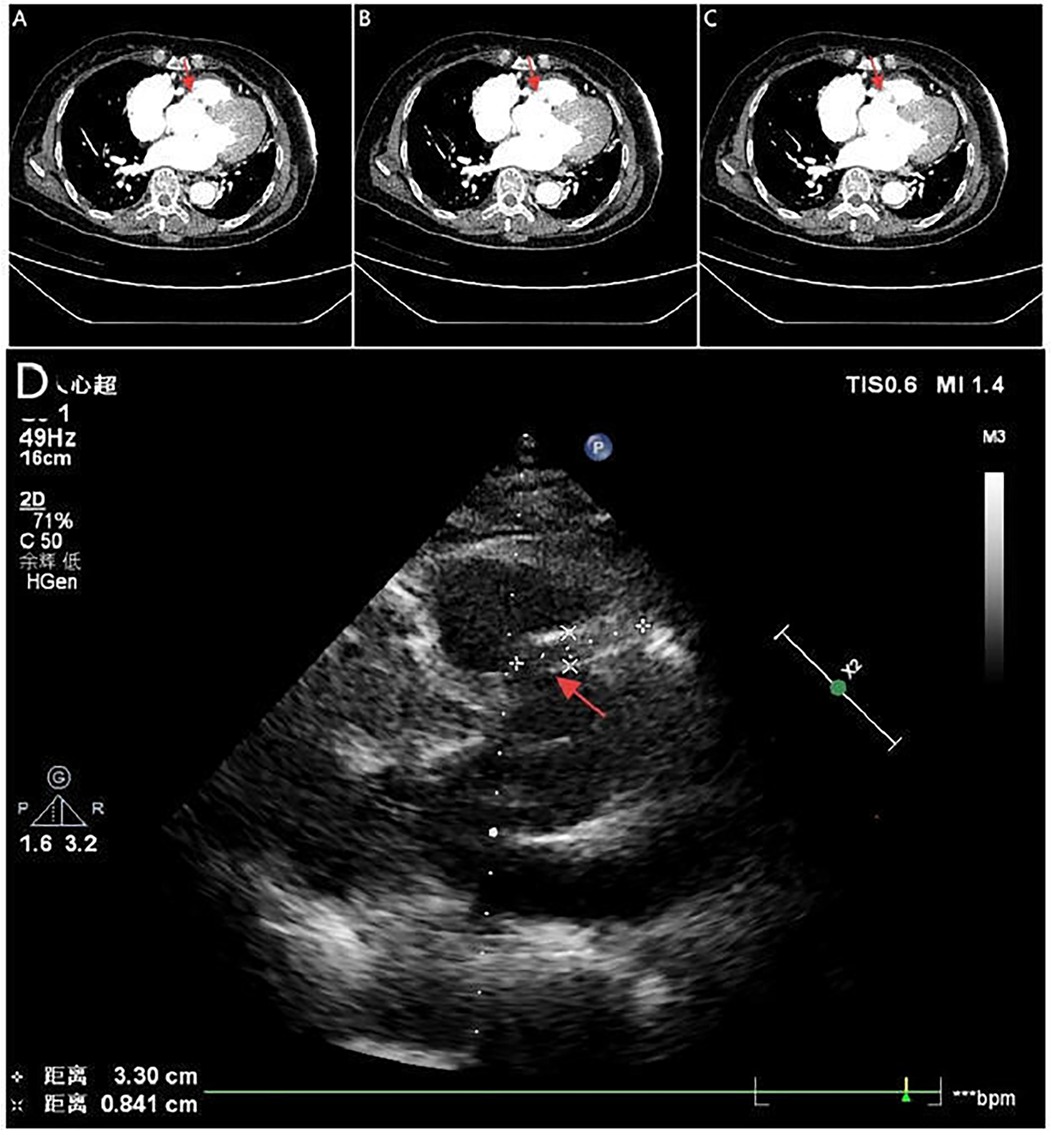

Figure 4

Serial CTA images (A–C) show located right coronary sinus of valsava dissection (red arrow). Echocardiography (D) demonstrates an intramural hematoma originating at the ostium of the RCA within the right coronary sinus, with partial extension into the proximal RCA (red arrow).

A 71-year-old woman with hypertension presented with chest tightness and diaphoresis. ECG revealed inferior STEMI and sinus bradycardia (Figure 3A). CAG demonstrated complete proximal RCA occlusion (Figures 3B–D; Supplementary Video 3) without visible intraluminal plaque on IVUS, but persistent extrinsic compression (Figures 3F–I; Supplementary Video 4). A drug-eluting stent (DES) was deployed at the ostium of the RCA with restored flow (Figure 3E). IVUS confirmed complete ostial coverage of the RCA and good stent apposition (Supplementary Video 6). CTA demonstrated mild aortic root dilation and right SOV dissection (Figures 4A–C; Supplementary Video 7). TTE demonstrated an intramural hematoma originating at the ostium of the RCA within the right coronary sinus, with partial extension into the proximal RCA (Figure 4D). The patient declined surgery and was managed conservatively. She remained stable with no recurrent symptoms during follow-up.

In the second case, the patient had long-standing hypertension and a normal coronary angiogram six years prior. IVUS clearly demonstrated extrinsic RCA compression by a hematoma extending into the perivascular space. Despite balloon angioplasty, no sustained TIMI 3 flow was achieved. In this setting, urgent coronary reperfusion was a critical step to stabilize the patient and create a window for potential aortic surgery (22, 23). This patient recovered without surgery. Serial CTA and echocardiography showed progressive regression of the right SOV dissection with septal echogenic band formation, indicating spontaneous healing. The favorable outcome of conservative management was attributable to a limited dissection entry and confined hematoma, the dual role of the stent in restoring perfusion and sealing the entry, strict hemodynamic control combined with close follow-up imaging surveillance (Supplementary Video 8). This case underscores the potential of conservative management in selected patients with restored coronary perfusion and anatomically stable lesions.